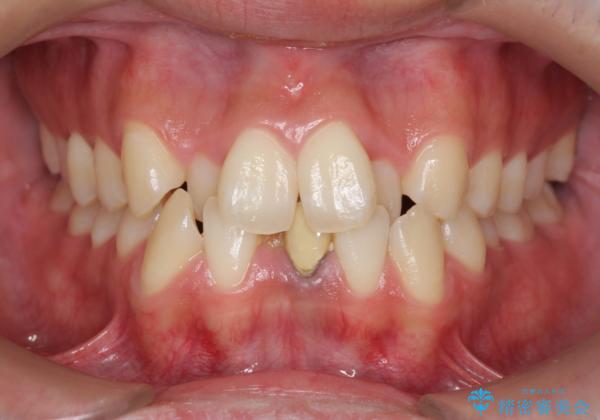

- 前歯のガタガタを主訴に来院。

下の前歯は一本保険治療での被せ物になっており、変色していました。

下の前歯が3本になり奇数になることで、上下の真ん中は一致しませんが、そこまで目立たないと思います。

ブラックトライアングルも少なめで、短期間でしっかり並びました。

上の前歯のガタガタも、わずかに歯を削って並べていますので、出っ歯になったりしないようにしています。